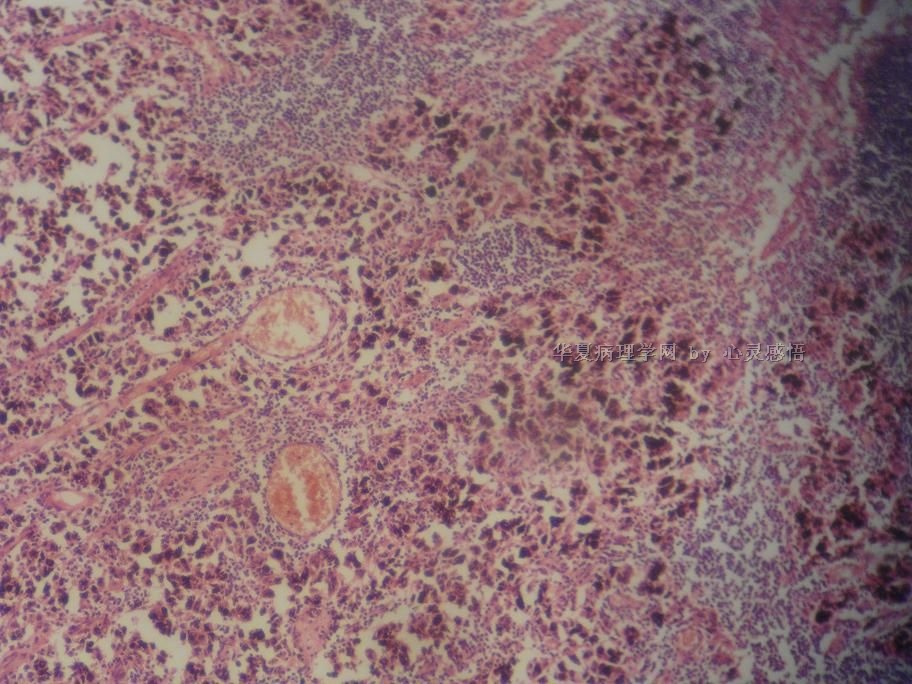

• 食道癌,淋巴结有没有转移,谢谢。图1

图1

1-6图是鳞癌。7-22图片无癌。

淋巴结没有转移

本帖最后由 于 2010-11-17 20:19:00 编辑  图14,19有转移

没有转移。

请教楼主;图片19是淋巴结吗?如果是应该是有癌转移!

没有转移,食道旁的淋巴结和肺旁的淋巴结相似,含有吞噬细胞。